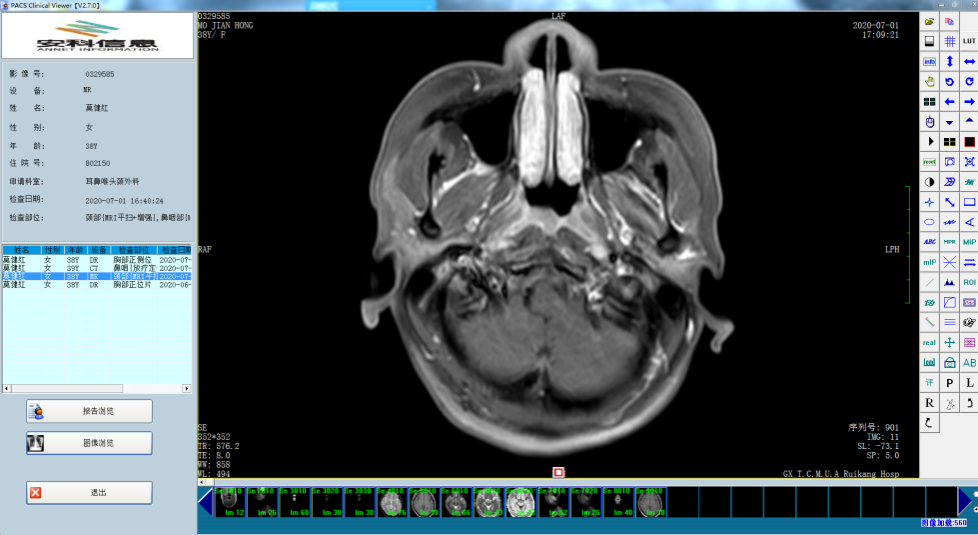

库欣综合征又称皮质醇增多症(hypercortisolism),是由于肾上腺分泌过多糖皮质激素导致的,主要表现为满月脸、多血质外貌、向心性肥胖、痤疮、紫纹、高血压、继发性糖尿病和骨质疏松等,长期不控制可能危及生命。库欣综合征按病因可分为促肾上腺皮质激素(ACTH)依赖型和非依赖型两种。经过内分泌医生检查,考虑陈女士为ACTH依赖型库欣综合征。ACTH依赖型库欣综合征又包括库欣病和异位ACTH综合征,有些异位ACTH综合征同部分库欣病的鉴别十分困难,两者在内分泌功能试验结果判读上有重叠,导致诊断不明而延误病情。简单的说就是,陈女士垂体或者身体其他地方长了一个肿瘤,这个肿瘤能够分泌内分泌激素导致她的身体内分泌紊乱,而医生需要确定这个肿瘤在哪里。经过检查发现陈女士垂体有一个绿豆大小的肿瘤,肺部也有一个花生大小的结节,常规的检查无法判断激素分泌是来自垂体瘤还是肺部结节,也有可能两个地方都不是。最有效的鉴别诊断方法是进行双侧岩下窦静脉采血(BIPSS)测定ACTH,这项技术能为库欣综合征做出精准的病因学诊断,被认为是确诊库欣病的金指标。因此,对于临床不好鉴别定位的库欣综合症,岩下窦静脉采血检测ACTH非常具有诊断价值。此外,通过比较左右侧岩下窦静脉ACTH的水平,可判断有无优势分泌侧,这对指导后续手术进行精准治疗意义非凡,且能帮助指导术中保存正常垂体组织,尽量减少术后垂体功能减退症现象。

经内分泌科与介入中心医生讨论,决定通过岩下窦静脉采血技术为患者采血测ACTH,该技术在我院首次开展,取得成功,同时标本处理也获得了我院转化医学中心的大力支持,经检测患者体内高内分泌激素水平分泌来自垂体肿瘤,拟近期为患者进行垂体肿瘤切除术。